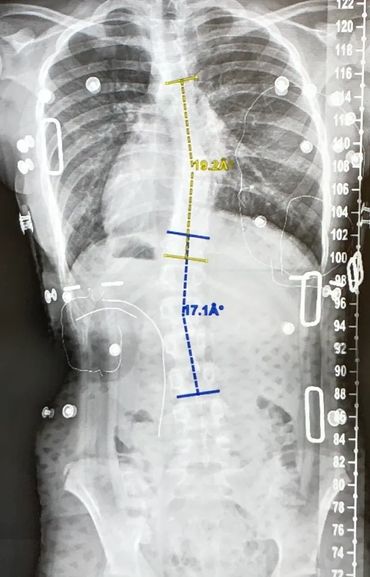

Hi! Above and to the side are some photos of my family, Liz (my brace doctor, who helps tweak and make adjustments to my brace), a couple of my X-rays and me. The side-by-side X-rays show my progress from right to left, The X-ray on the right shows my spine before I got a new brace (since I grew out of my old one) and the picture on the left illustrates my back one month after I got the new brace!